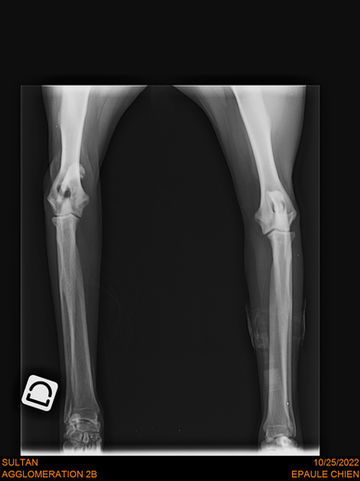

Joey wurde erfolgreich operiert, jetzt macht er fleißig Physio und dann denken wir kein sein Leben beginnen

Joey ist ein junger Cocker Rüde, den wir in seiner Not aufgenommen haben. Da der kleine Genosse öfters mal mit seinen Zähnen versucht seinen Willen durchzusetzen und dazu noch einen alten Schulterbruch hatte, war er einer der Nächsten, der eingeschläfert worden wäre.